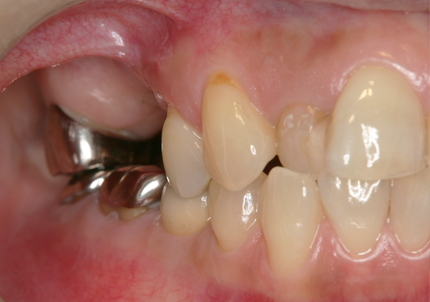

1.初診時口腔内(2007年6月30日)

2.右側上顎洞サイナスリフト後にインプラント埋入

↑ サイナスリフト術前

↑ サイナスリフト術後

3.右上インプラント補綴物装着(2009年7月24日)

↑ 右上サイナスリフト後にインプラント埋入